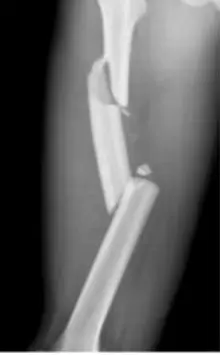

Which pattern of fractures is demonstrated in the attached X-ray?

- B. Segmental